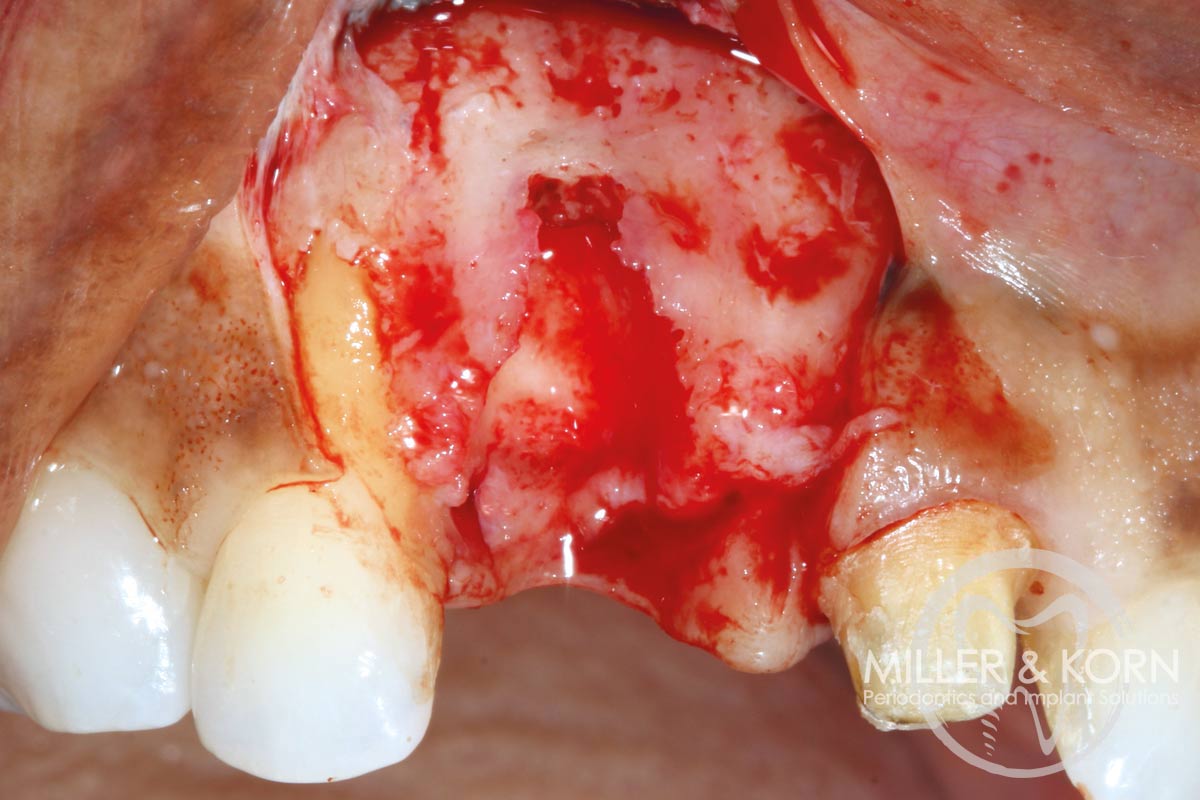

4/22 - Full thickness flap elevation with vertical releasing incisions. Note, significant apical and buccal bone resorption after raising the flapImmediate implant placement and regeneration of ridge using an allograft bone ring and Jason® membrane - Drs. Miller and Korn